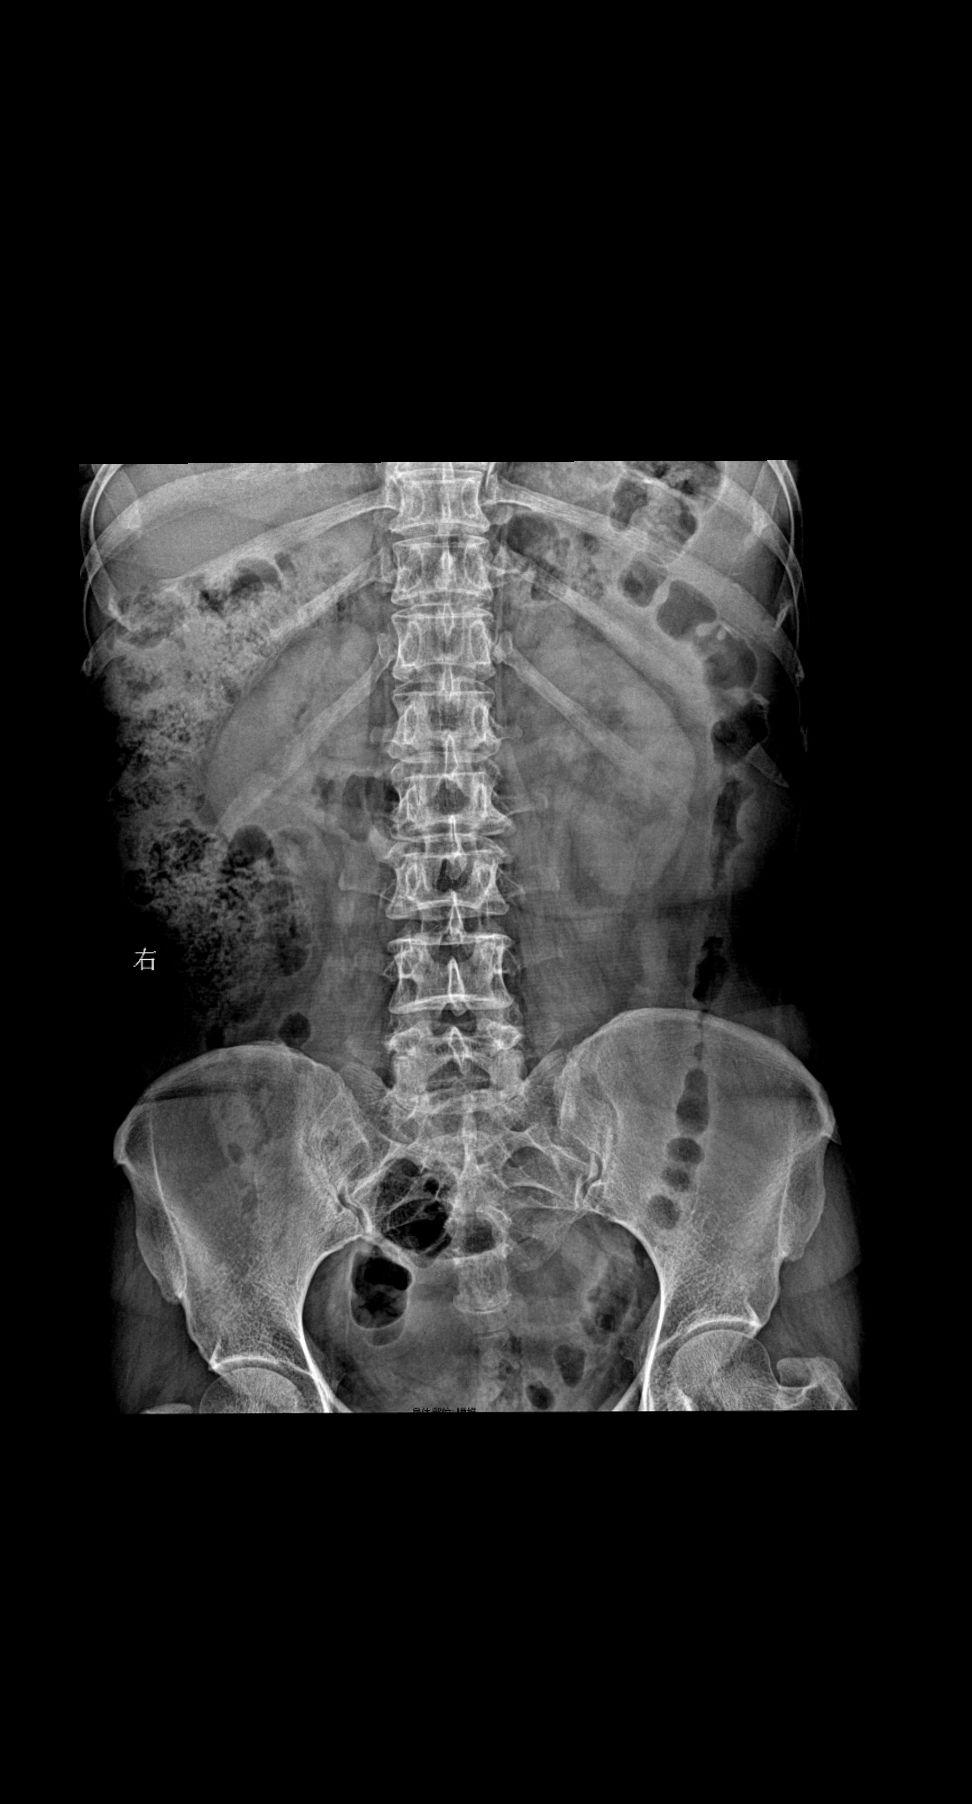

女 26 右侧腰背部疼痛 腰椎正侧位